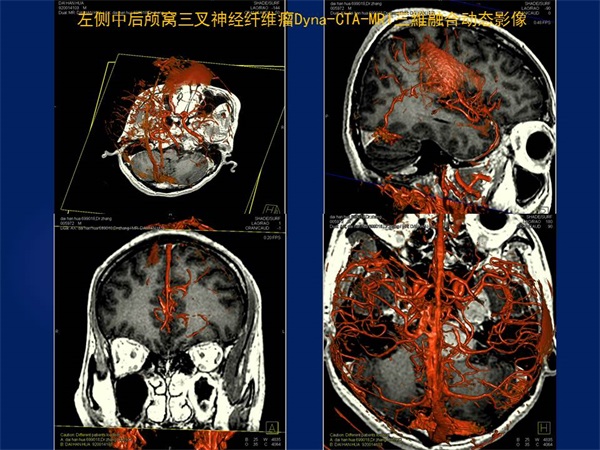

马廉亭,男,80岁,军队专业技术1级教授、博导,文职1级将军,河南安阳人,1954年毕业于安阳师范学校初中第一班、1957年毕业于安阳市第一高级中学、1962年河南医学院医疗系本科毕业入伍,现任广州军区武汉总医院博士后科研工作站站长,曾任中华医学会神经外科学分会常务委员、世界华人神经外科联合会常务委员、全军神经外科专业委员会副主任委员、中南六省(区)及湖北省神经外科学会主任委员、湖北省科技期刊编辑学会副理事长,国家、全军、省、军区及联勤部科技奖及科研基金评审委员会委员,军区、联勤部及医院职称评审委员会委员、主任委员等20多项社会兼职,中华实验外科、中华外料、中华神经外科、觧放军医学、中国临床神经外科等20余种杂志总编、副总编、编委。善长脑神经外科各种疑难病,尤其是脑脊髓血管病的诊治,更精于脑、脊髓血管疾病的血管内治疗,1979年在国际上率先将介入技术应用于颅脑血管战伤的治疗,1983年在国内率先开展血管内神经外科(介入神经放射学),为我国血管内神经外科创建人之一。撰写论著240余篇、主编《脑脊髓血管病血管内治疗学》、《微侵袭神经外科学》、《创伤性假性动脉瘤与动静脉瘘》等连同本书共9部署作,参编《黄家驷外科学》、《手术学全集·神经外科卷》、《临床神经外科学》、《神经病学》等20部著作。获国家科技进步二等奨2项、三等奖1项、省部级与军队科技进步二等奖13项,国家”九五”攻关课题1项、多项省部级及军队科研基金。荣立三等功5次、1998年带领科室参加抢救抗洪抡险伤员生命、为保障部队战斗力做出贡献科室荣立集体二等功、2000年8月29日江泽民主席簽暑通令荣立二等功,享受政府特殊津贴,,获中国医师奨、王忠诚中国神经外科医师终身成就奖、全国优秀科技工作者、全军优秀科技工作者、省科技精英与白求恩式的卫生工作者,2000年将荣获的科技重奖20万元全部捐给医院作为医院培养中青年高端科技人才启动基金、从此医院建立了以【马廉亭】名字命名的医院岀国培养中青年人才奖励基金。多次被中央电视台《祖国在我心中》、《东方之子》及多家报纸、杂志、书刊介绍其先进事迹。75岁退出现役后仍坚持继续在临床从事医教研工作、带领科室同志开展医学影像三维融合技术在神经系统疾病中的临床应用研究,并创造性地研究出"动态三维立体解剖影像融合技术",同時将融合后获得的影像命名为"动态三维立体解剖融合影像”。

《三维影像融合技术在神经系统疾病诊治与研究中的应用》